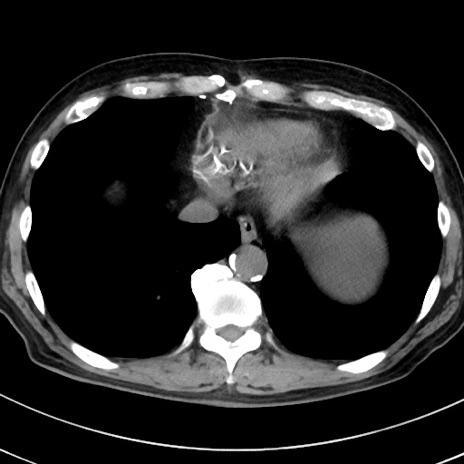

症例38(横断像)

【症例】70歳代 男性

【主訴】腹痛・嘔吐

【現病歴】昨晩より、嘔吐・腹痛あり。今朝になっても嘔吐あり。来院。

【既往歴】心臓バイパス手術、開腹胆摘、腸閉塞

【身体所見】BP 107/71mmHg、HR 116/min、腹部:平坦、軟、下腹部に軽度圧痛あり。反跳痛なし。

【データ】WBC 15100、CRP 0.32